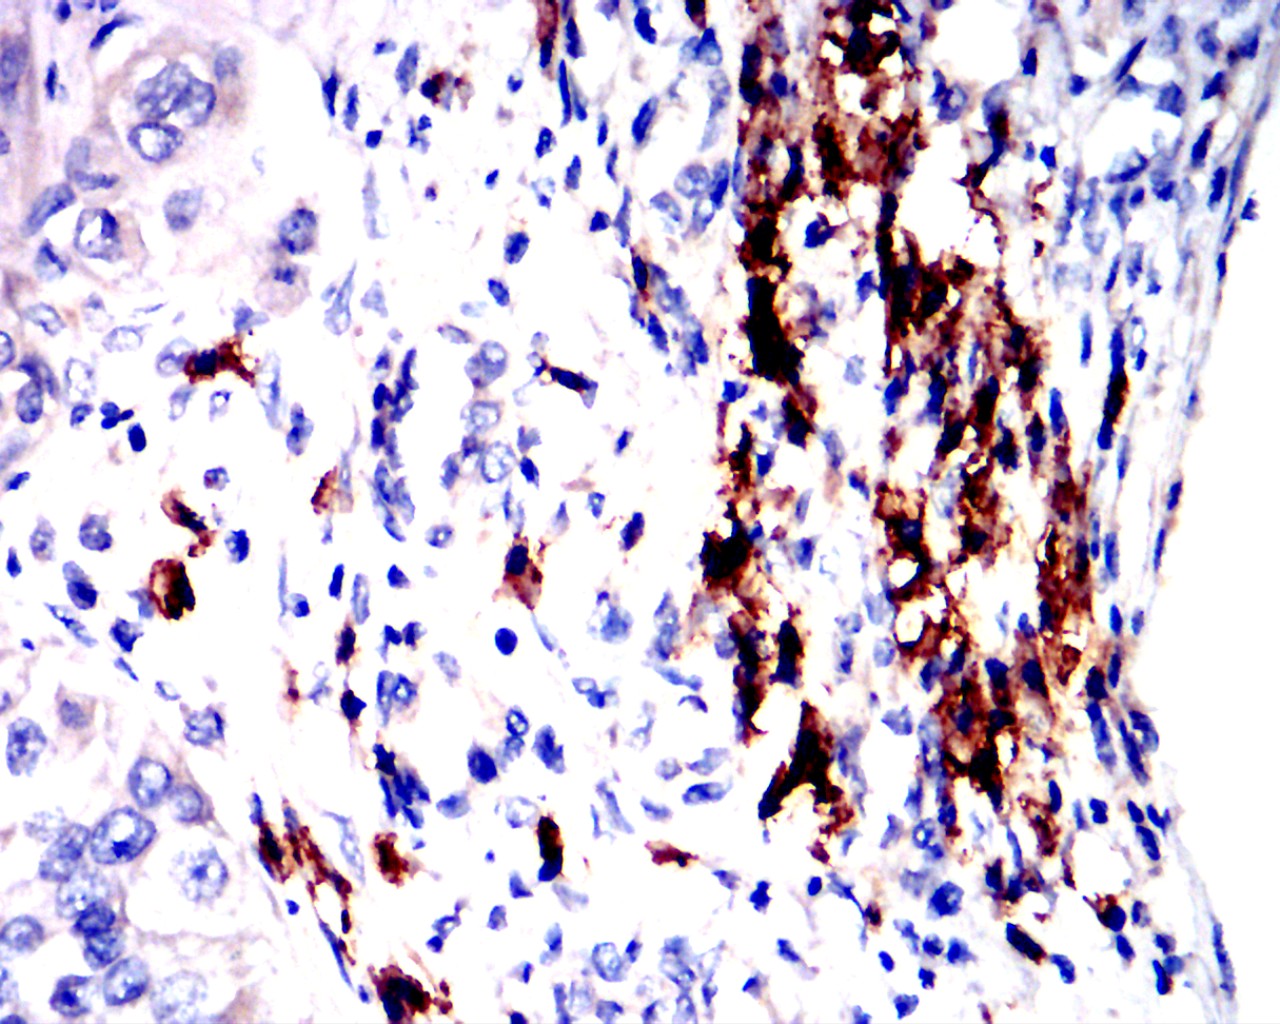

分类: 科研抗体货号: 90005别名: IL-1; IL1F2; IL1beta; IL1-BETA应用: IHC,IF,FCM反应种属: Human